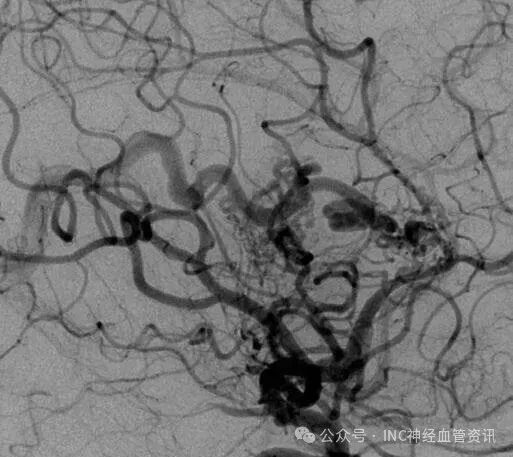

Anna的AVM由多条动脉供血:ACA/PcaA分支、ACoA穿支和mPChA,形成了一个复杂的血管网络。首次伽马刀治疗后,血管团部分闭塞,但残留的畸形血管仍然构成出血威胁。

▼该AVM由ACA/PcaA分支、ACoA穿支和mPChA供血[右侧ICA造影